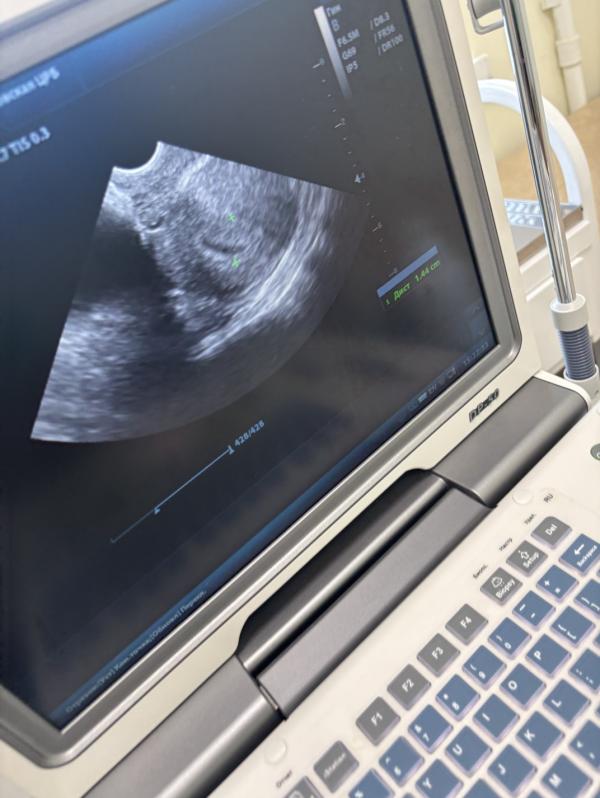

Эндометрий 14 мм это норма задержка и киста фолликула 6.5мм фото матки

Это может означать скоро мес ?

Если бы тесты молчат завтра первый день задержки